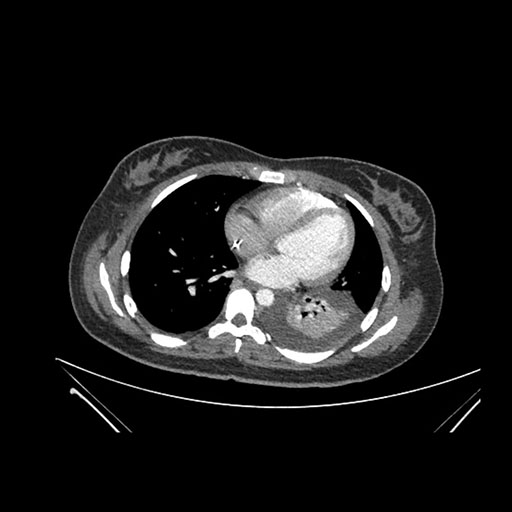

Imaging Analysis

Look through the patient's CT scan to identify any areas of concern for the necessary procedure.

Axial Arterial

Based on initial findings, which issue(s) would you be most concerned about?